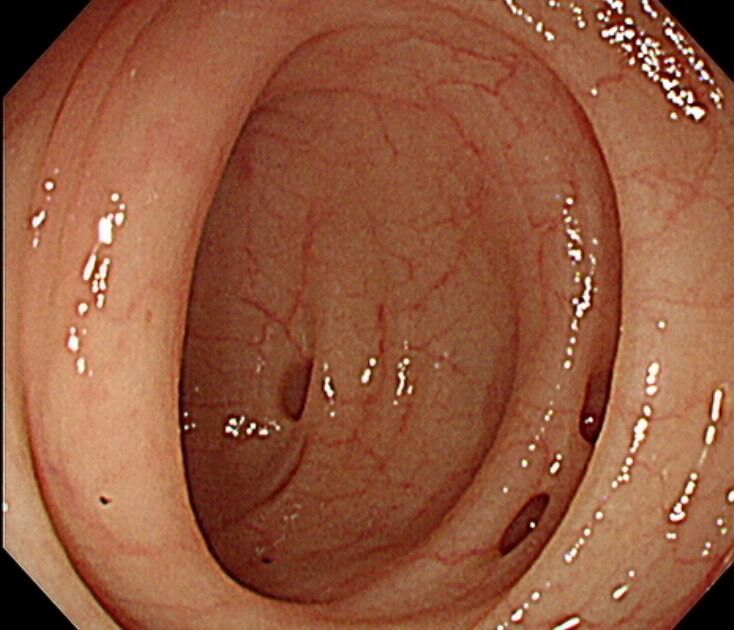

為什麼會有大腸憩室?你可以想像,就像年紀漸漸大了,皮膚的彈性會變差,50歲以後,大腸的肌肉層,也會變得比較脆弱、鬆弛。如果平常大腸用力收縮,企圖把糞便跟腸氣往下送時,就可能在大腸肌肉層結構較薄弱的位置,形成大腸憩室。所以做大腸鏡檢查時,腸壁看起來會像吹氣球一樣擠出一個個凹陷的「泡泡」,這就是大腸憩室。(編輯推薦:腸子有凹洞,發炎嚴重竟致穿孔阻塞!大腸憩室炎7個症狀別耽擱)

絕大多數的大腸憩室,並不會造成困擾,可以和平共存,往往是在做大腸鏡檢查時,意外被發現,若無症狀也不需要特別治療。不過,若大腸憩室反覆發炎或流血,導致腹痛、貧血或生活品質下降,醫師就會評估是否需要手術,把憩室集中的那一段大腸切除,避免問題一再復發。